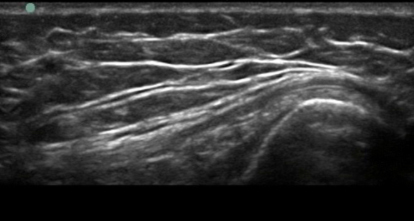

Knee Pes Anserine Long Axis Image